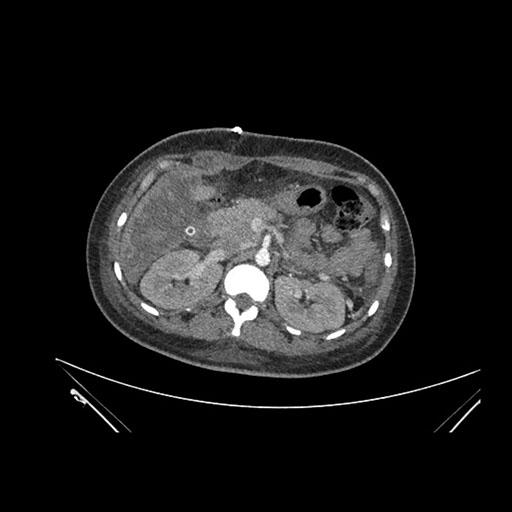

Coronal Venous

Imaging analysis

Based on initial findings, which issue(s) would you be most concerned about?